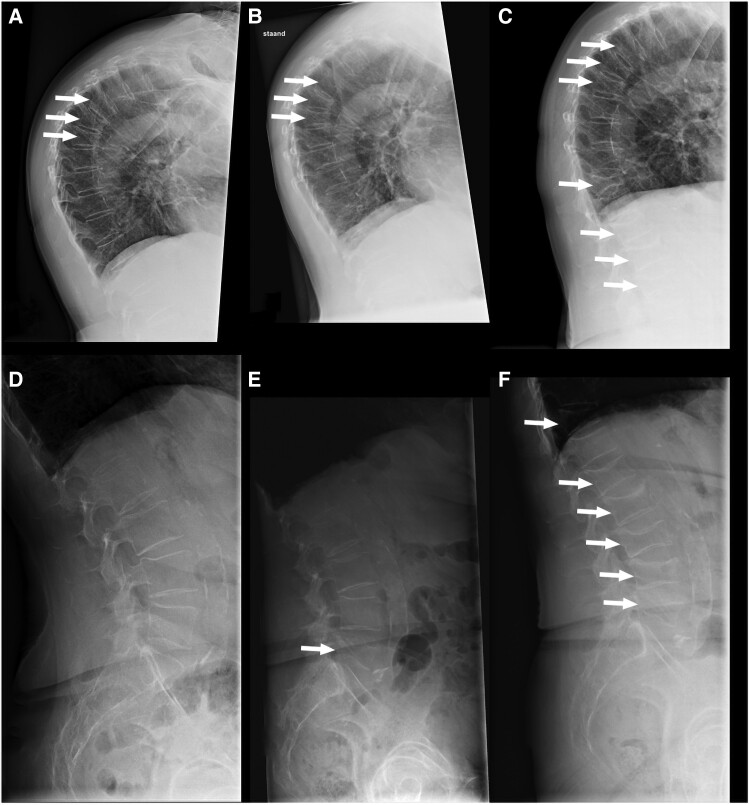

A defect in the canonical Wnt-β-catenin pathway may lead to reduced bone strength and increased fracture risk. Sclerostin is a key inhibitor of this pathway by binding to low-density lipoprotein (LDL) receptor-related protein (LRP)-5/6, thereby reducing bone formation. The effectiveness of romosozumab, a human monoclonal antibody that binds sclerostin and prevents this inhibitory effect, has been questioned in patients with inactivating genetic variants in LRP5 or LRP6. We present a 67-year-old woman with severe osteoporosis with 4 grade 2 vertebral fractures due to a heterozygous pathogenic variant in LRP5. She was treated with romosozumab for 1 year, after which a routine follow-up spine x-ray revealed 5 new vertebral fractures, despite a strong increase in bone mineral density (BMD) (lumbar spine [LS] + 58%; femur neck [FN] + 23%), although overestimated at LS because of the vertebral fractures. This suggests that in patients with loss-of-function LRP5 variants, romosozumab is able to increase BMD. However, it is unclear whether the progressive vertebral fractures are due to the severe osteoporosis in relation to the start of romosozumab or a diminished responsiveness related to her LRP5 variant. Further evaluation is needed on the effect of romosozumab on BMD and fracture outcomes in patients with a likely defective LRP5/6 receptor.